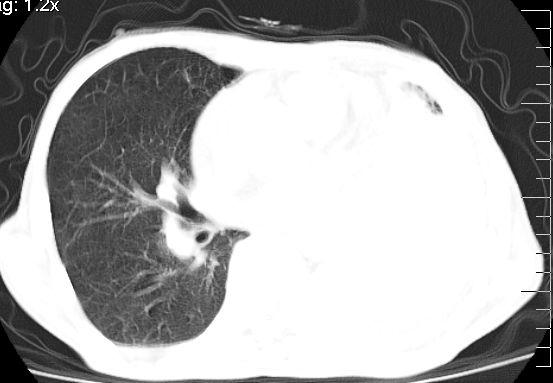

标题: CT10141:男、84岁,咳嗽、咯血1年。 [打印本页]

标题: CT10141:男、84岁,咳嗽、咯血1年。

支持左侧中央型肺癌伴下叶肺不张\\纵隔淋巴结转移.左侧包裹性胸腔积液\\心包积液.左侧少量胸腔积液..慢性支气管炎伴部分间质纤维化.

左肺中心性肺癌并肺不张,同侧 胸膜及心包转移,左肺癌性淋巴管炎

左肺中心性肺癌并左肺下叶肺不张,纵隔淋巴转移、同侧胸腔及心包积液(转移)。